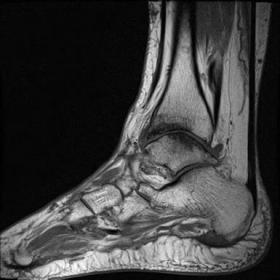

Semantic Segmentation and Object Detection for 3D Motion Analysis of the Ankle Joint in High-Resolution MRI

Although high-resolution MRI provides excellent anatomical detail, existing segmentation approaches possess a requisite yet inadequate level of precision, require substantial human effort, and fail to accurately represent the intricate 3D structure. To address these limitations, this work develops a novel 3D Faster R-CNN engine that automatically detects and segments the main ankle joint components from volumetric MRI. The proposed design combines a 3D ResNet-50 transformer with a 3D Region Proposal Network and 3D ROI Align components to analyze MRI scans. The model trained with experiments based on ankle MRI datasets from second-party repositories used data processing steps to normalize image size and enhance dataset collection. The assessment metrics consisted of Dice Similarity Coefficient, Intersection over Union, and mean Average Precision (mAP). By evaluating several models, the system achieves a Dice coefficient score of 91.4% alongside an mAP of 89.6% at IoU 0.5 which beats previous 2D and 3D segmentation techniques. Scientific images showed that the method could precisely detect body structures in different MRI views while keeping their correct shapes.